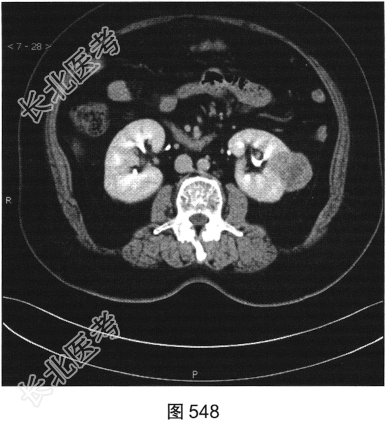

- 多项选择题3.[提示]CT平扫+增强(图545~图549):左肾下极背外侧软组织密度灶, 部分突出于肾实质外,其内可见低密度坏死灶, 增强扫描强化不均匀,平扫、皮质、实质、排泌CT值36HU、92HU、73HU、53HU。可考虑的鉴别诊断为( )

A、肾嗜酸性粒细胞腺瘤

B、出血性囊肿

C、肾血管平滑肌脂肪瘤

D、肾细胞癌

E、肾转移瘤

F、淋巴瘤